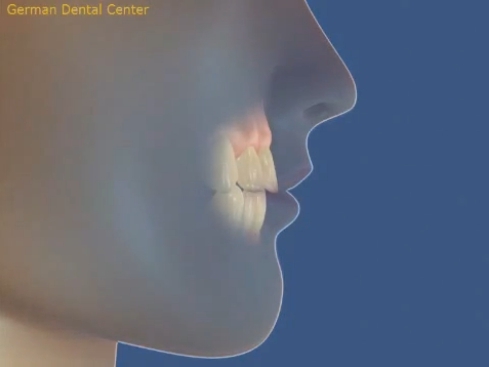

- Исправление прикуса